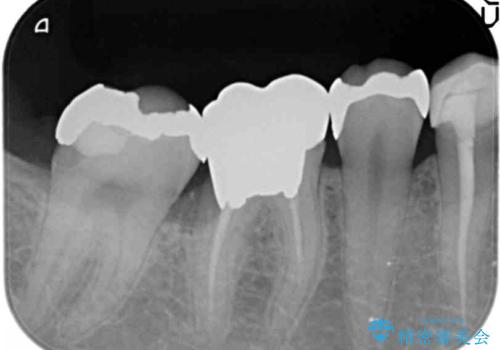

右下の奥歯の虫歯が大きく、やりかえが難しい状態でした。

外して虫歯を取ったところ。歯茎の深いところまで虫歯があり、やむなく抜歯しました。

右下7については、遠心の歯の高さがなく、また、同様に歯肉縁下にカリエスがあったため、手術を行い改善しました。

右下6については、物理的には歯を使うことは可能ですが、残すと悪くなっていくのを避けられないような修復しかできないため、長期的な展望が立たないため抜歯をお勧めしました。